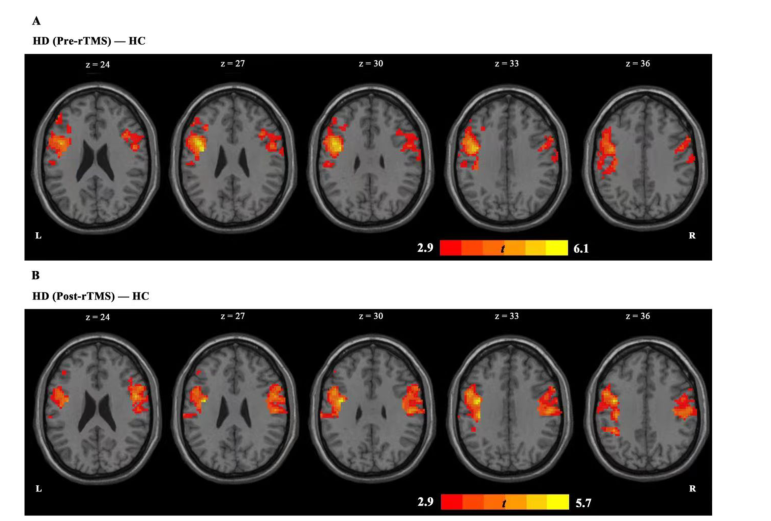

上圖顯示,在基于 PCC 的分析中,我們發(fā)現(xiàn) HD 組與 HC 組相比表現(xiàn)出 PCC-左額下回,PCC-右側(cè)中央前回耦聯(lián)增加。

在完成 7 個(gè)療程的 rTMS 療程后,HD 組的 PCC-左額下回耦合異常增加后出現(xiàn)了減少,并在HC組表現(xiàn)出類似的趨勢(shì)。但在治療后,(HDvsHC)pcc-右中央前回耦聯(lián)持續(xù)存在。